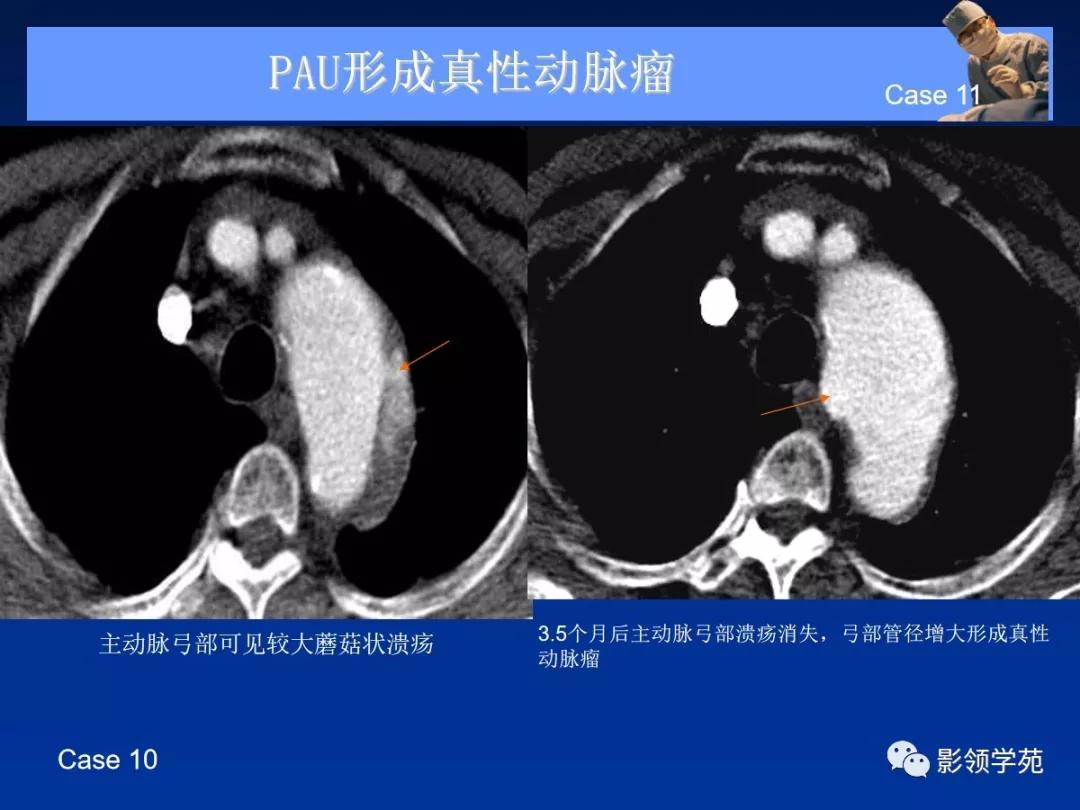

- 主动脉穿通性溃疡( penetrating aortic ulcer, PAU )